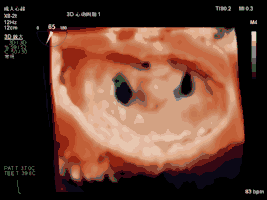

夾合術(shù)中(左房面觀):三維心超示夾合后雙孔征

夾合術(shù)中(左室面觀):三維心超示夾合后雙孔征